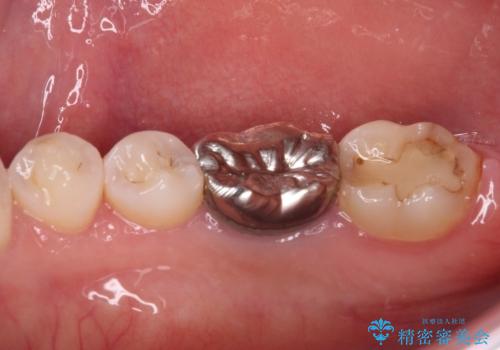

- 奥歯の銀歯が外れたことをきっかけに、全ての銀歯をセラミックに替えたいとのことで来院された患者様です。

第一大臼歯4本と、メタルインレーが装着されている2歯をセラミッククラウンならびにセラミックインレーにて補綴治療・修復治療を行うこととしました。